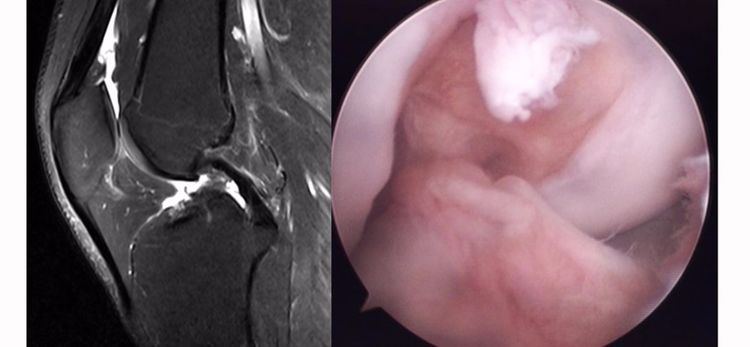

ACL损伤的MRI分级——

Grade1:韧带内损伤,无长度改变。

Grade2:韧带内损伤并长度延长。

Grade3:完全性韧带撕裂。

Grade1、2级为韧带的部分损伤,Grade3级为韧带的完全断裂。